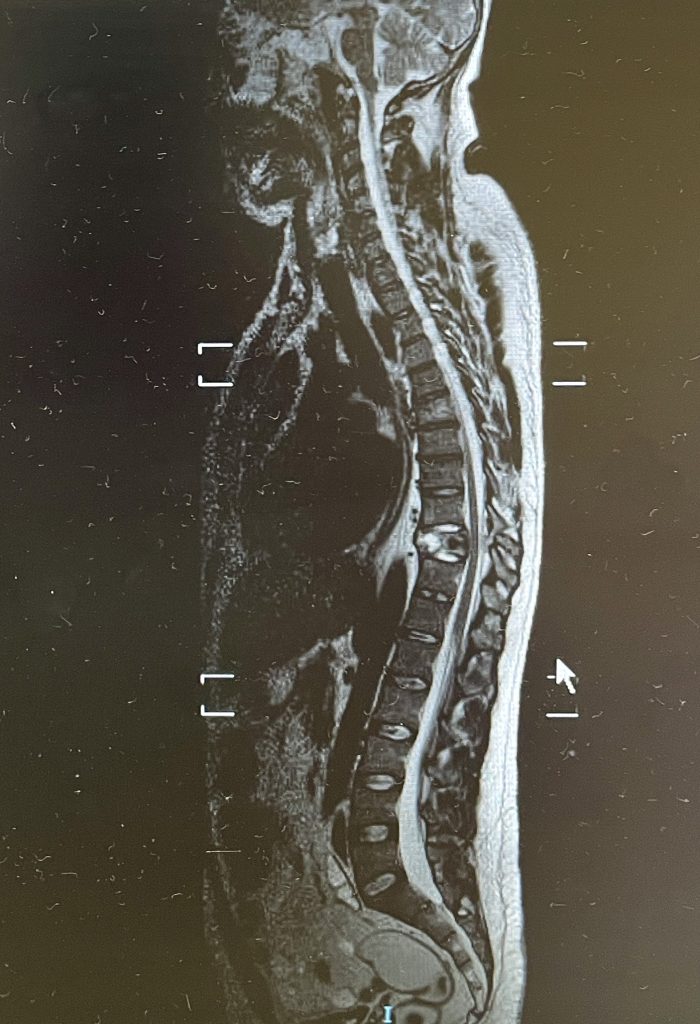

La osteoporosis es una enfermedad esquelética en la que se produce una disminución de la densidad de masa ósea. Así, los huesos se vuelven más porosos, aumenta el número y el tamaño de las cavidades que existen en su interior, son más frágiles, resisten peor los golpes y se rompen con mayor facilidad.

Las fracturas más frecuentes son las vertebrales, las de cadera y las de la muñeca.

La cementación vertebral es un tratamiento contra el dolor, que consiste en introducir de manera percutánea cemento dentro de una vértebra fracturada, a través de una cánula. Previamente se intenta la corrección de la deformidad vertebral mediante el uso de unos balones hinchables.